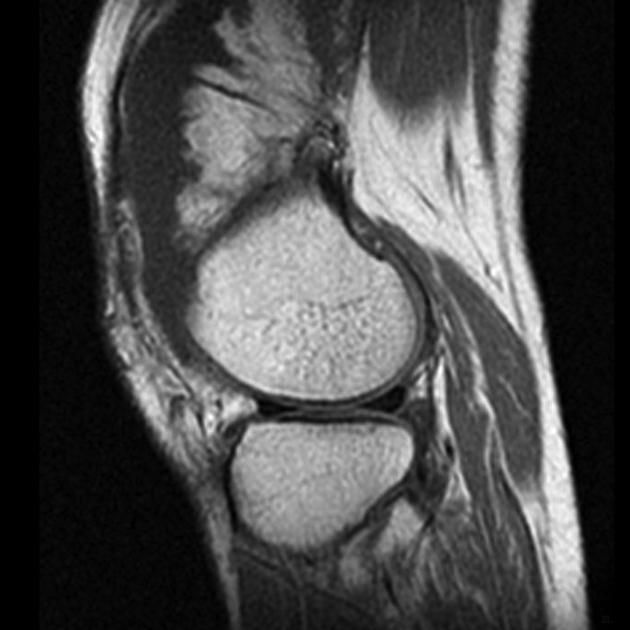

Frond like fatty tissue affecting the joint or bursa

Lipoma Arborescens

5th-7th decades

Bright on T1 and T2 and saturates on fat sat sequences